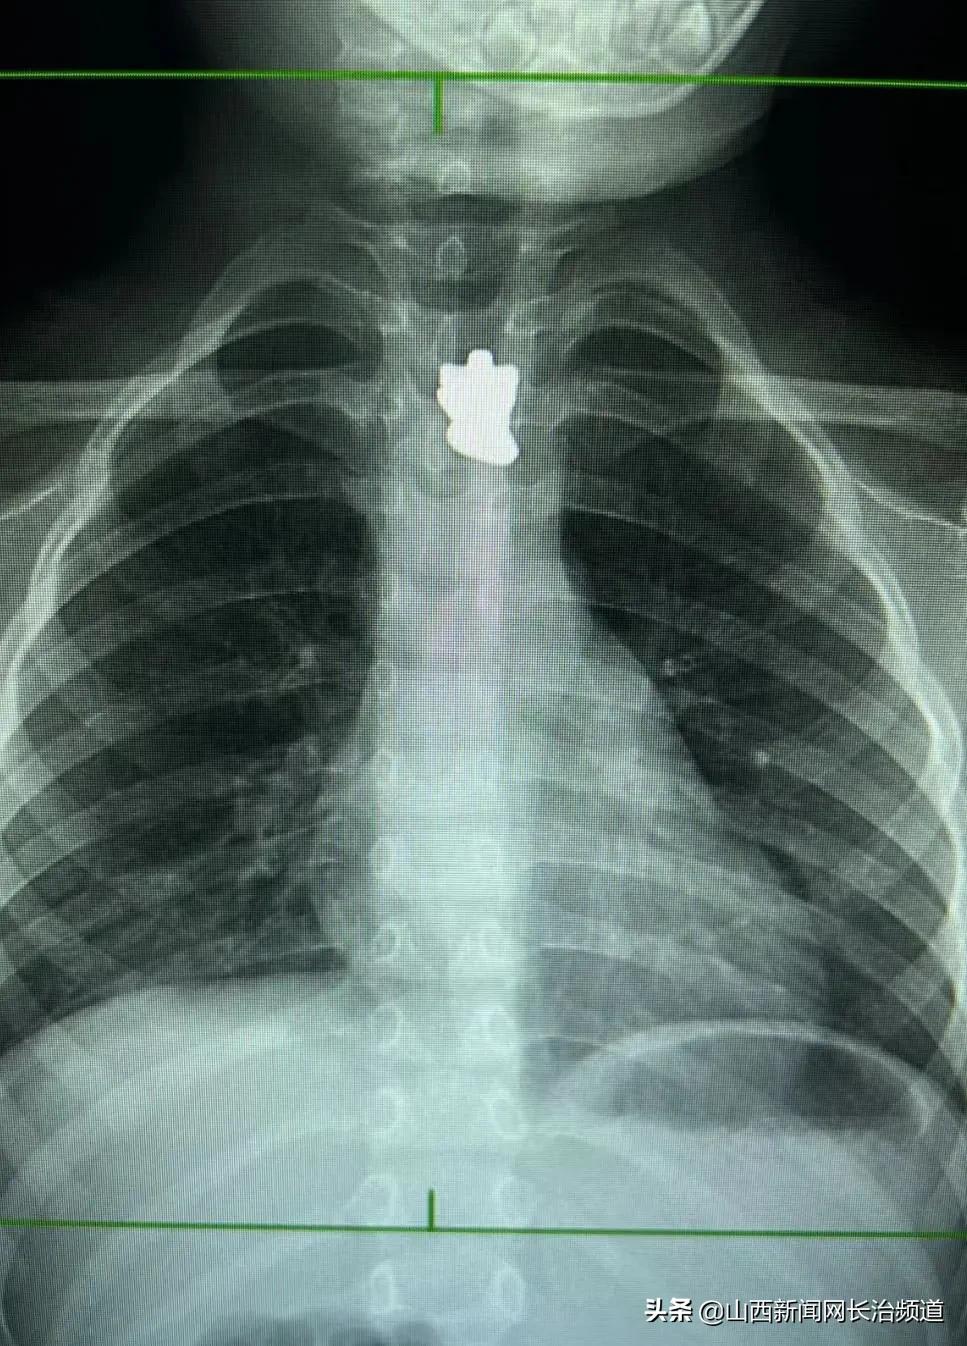

❀ 拍胸片时,检查部位要去除可能遮挡的组织、形成伪影的物品,比如硬币、项链、衣服上的拉链和装饰品等。儿童性腺器官需要用铅衣遮挡。

像这样,是不行滴哦!